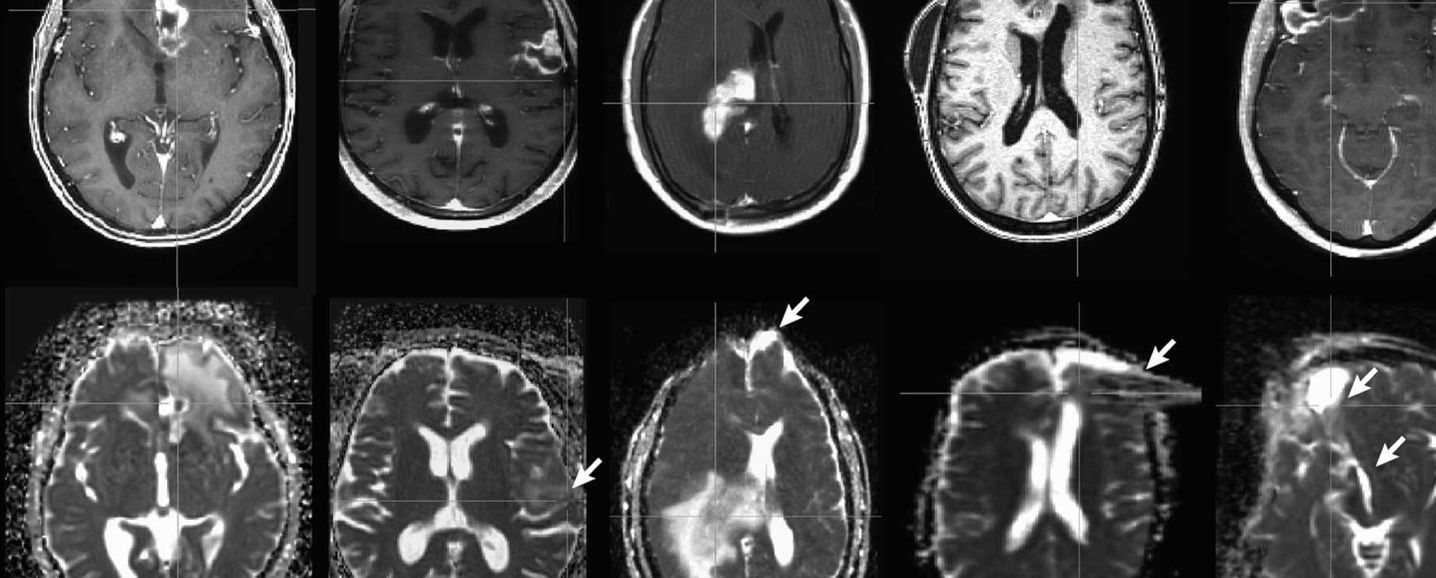

Developing image acquisition and reconstruction techniques using MRI physics